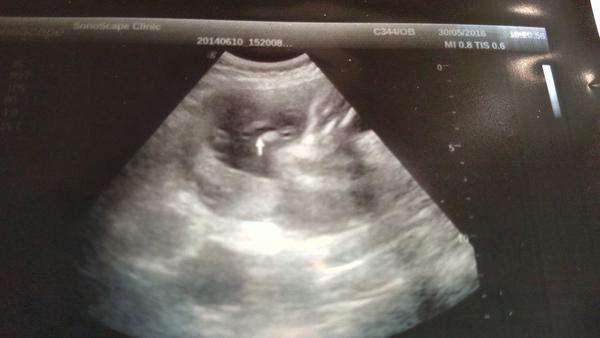

@estrellita uz jsem je tu vkladala prvni foto pred 2 lety jasny kluk..druhe fito nynejsi tehotenstvi ze 16tt a treti foto z 24tt.